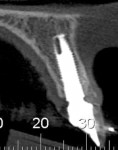

When the patient was 18 years old, root fracture of tooth No. 8 occurred, which was an indication for extraction (Figure 1 and Figure 2). Six months later, tooth No. 9 was also designated for extraction due to recurrent periapical lesions (Figure 4 and Figure 5). The following treatment plan was established: extraction of teeth Nos. 8 and 9 and performance of IDR at two different times (Figure 3 through Figure 11); placement of two ceramic abutments and all-ceramic crowns (Figure 12 through Figure 15); and continued orthodontic treatment to finalize the case.

The same procedure was used for tooth No. 9. Six months after the second procedure, definitive restorations fabricated from zirconia-ceramic were placed for both central incisors. The patient was clinically and radiographically followed every 6 months. Figure 12 through Figure 15 show the occlusal and buccal clinical aspect at 3 years follow-up, and Figure 16 and Figure 17 show the tomographic follow-up of the buccal plate bone.